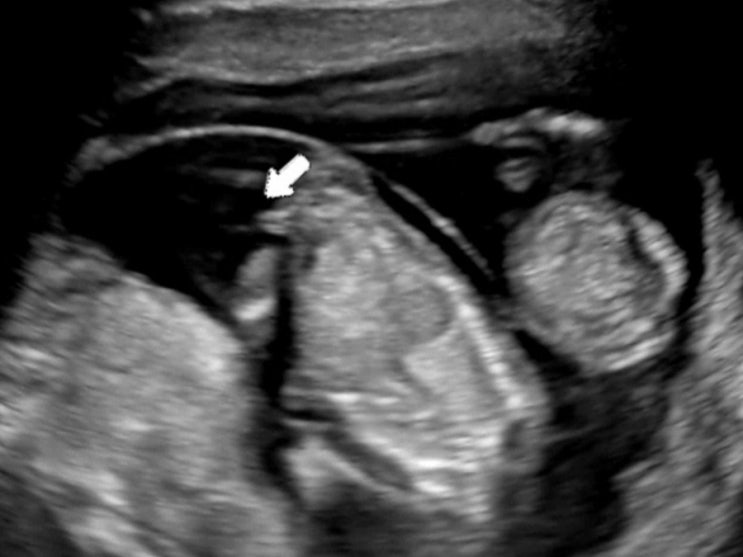

#16 [임신20주차] 쌍둥이임신 / 아들둥이 / 수원 베이비페어 / 쌍둥이 육아용품 / 정밀초음파 / 두나 플러스 카시트

8/12 ~ 8/13 주말동안은 수원에서 열리는 베이비페어에 다녀왔다. 일단 비싼 육아용품..🥲 위주로 가격을...